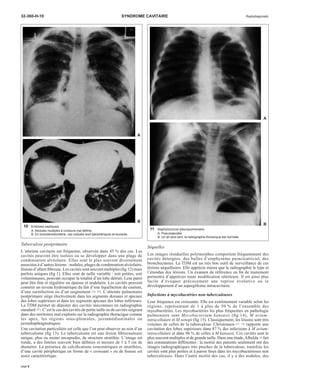

6 Aspergillose invasive. Fièvre pro-longée

chez un patient sortant de son

aplasie thérapeutique.

A. Nodules pulmonaires multiples.

B. La tomodensitométrie montre

des « croissants » gazeux dans

ces nodules.

B